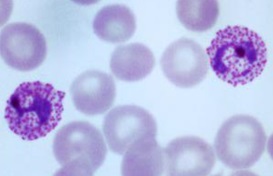

This organism falls within phylum:

Apicomplexa

Euglenozoa

Radiolaria

Chlorophyta

And what is the organism?

Phylum: Apicomplexa

Organism: Plasmodium vivax

What is the phylum Apicomplexa?

Plasmodium is a parasite living in blood of mammals and birds that causes malaria; carried by Anopheles mosquitoes.